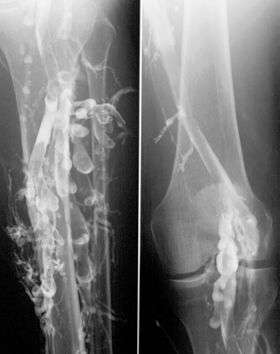

![]() Phlebography in a patient with deep venous thrombosis. | |

Venography (also called phlebography or ascending phlebography) is a procedure in which an x-ray of the veins, a venogram, is taken after a special dye is injected into the bone marrow or veins. The dye has to be injected constantly via a catheter, making it an invasive procedure. Normally the catheter is inserted by the groin and moved to the appropriate site by navigating through the vascular system.

Contrast venography is the gold standard for judging diagnostic imaging methods for deep venous thrombosis; although, because of its cost, invasiveness, and other limitations this test is rarely performed.[1]